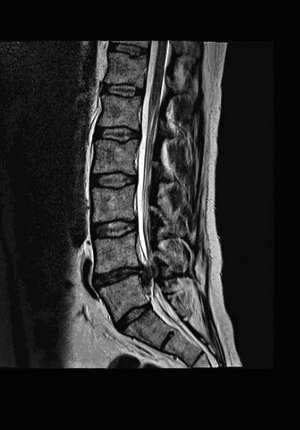

Diese wird jedoch nur in Abhängigkeit von einem natürlich korrelierenden klinischen Krankheitsbild und entsprechend radiologisch gesichertem pathologischem Befund mittels weiterführender Diagnostik (in der Regel eine Magnetresonztomographie der Wirbelsäule) umgesetzt.

MRT-Aufnahme der Lendenwirbelsäule, zeigt Bandscheiben und Wirbelkörper.

Bei einer akuten lumboischialgiformen (ins Bein ausstrahlenden) und dermatombezogenen Klinik mit möglichen neurologischen Störungen (motorisch und sensorisch) sowie einem chronifiziertem Schmerzsyndrom bei entsprechend radiologisch gesichertem Bandscheibenvorfall steht die Indikation zur Mikrodiskektomie desselben.

In unserer Klinik wird eine offene mikrochirurgische Operation unter Zuhilfenahme eines Operationsmikroskopes als Standardverfahren gewählt. Eine spezielle perioperative Lagerung zur Minimierung der Operationsrisiken wird umgesetzt.